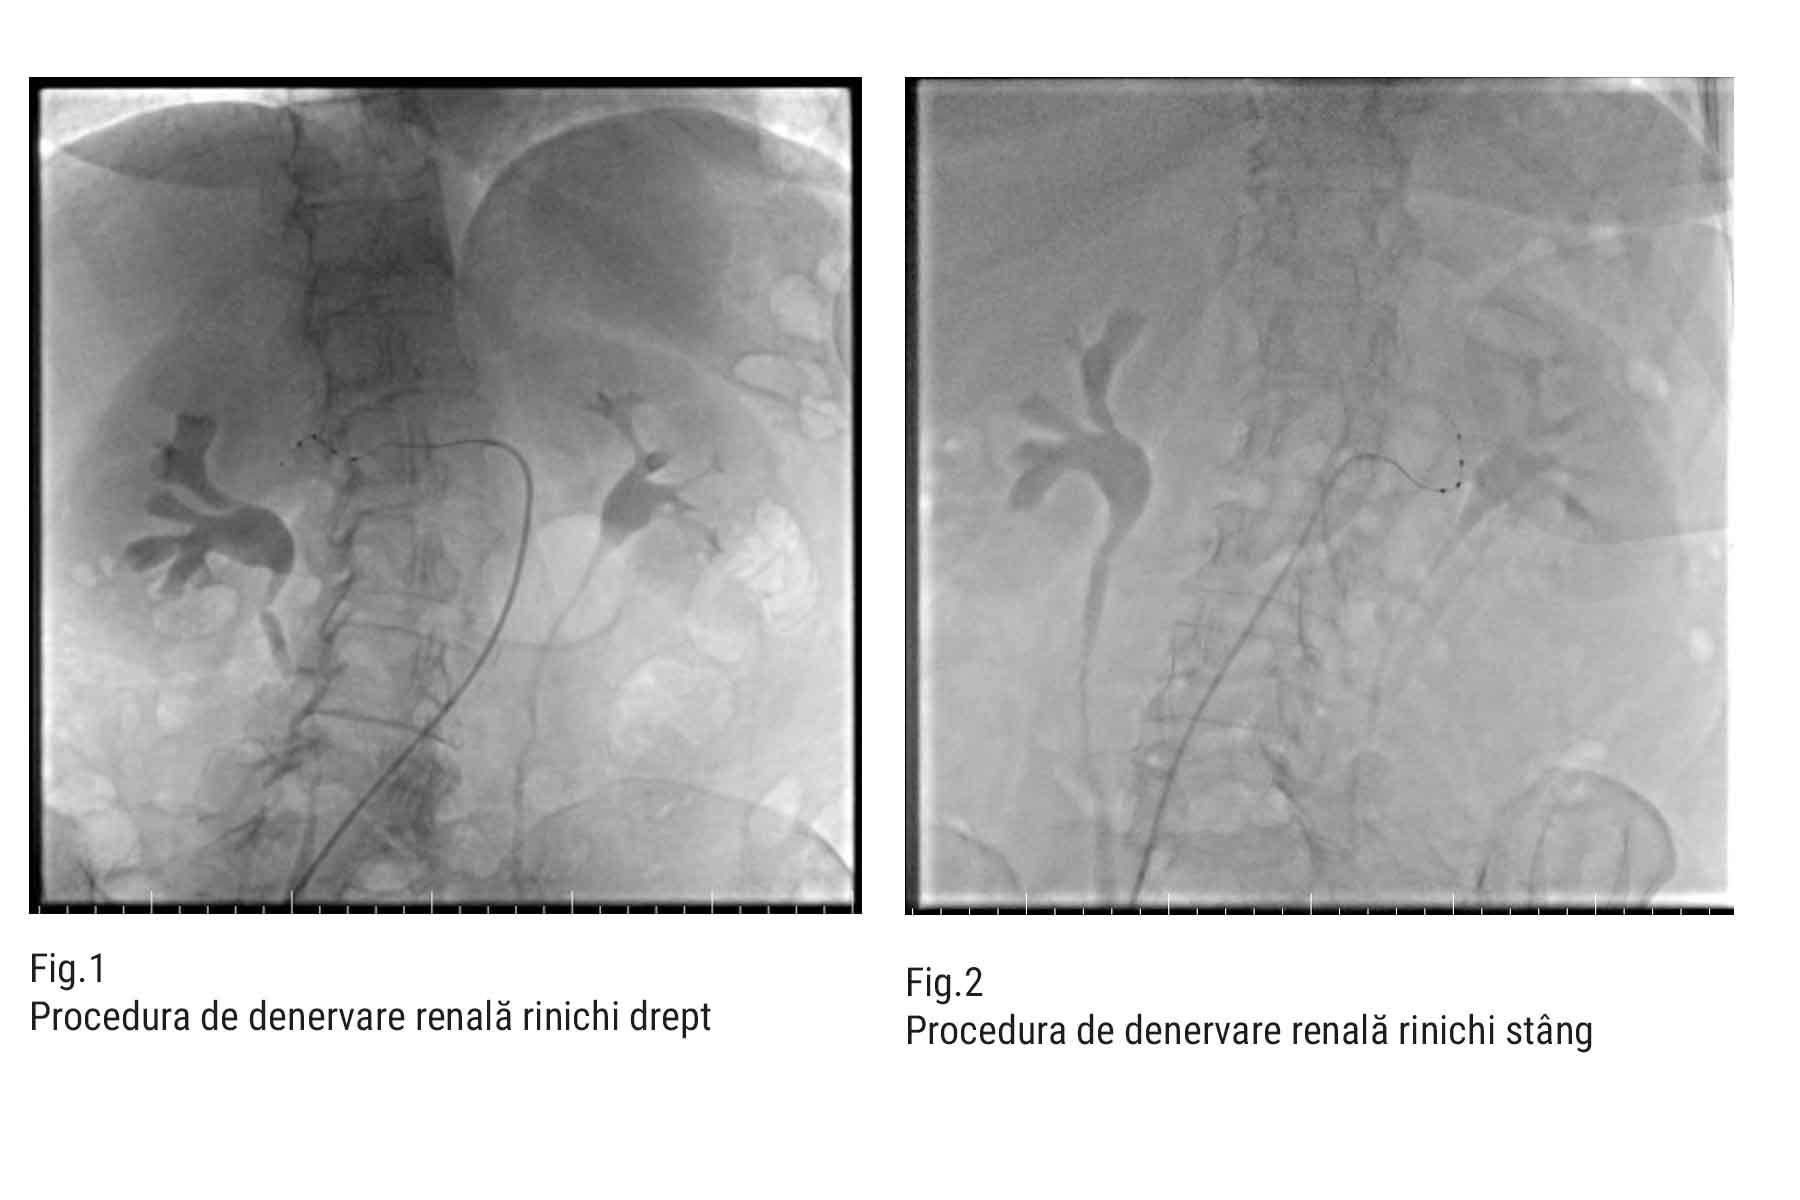

Procedura de denervare renală este microinvazivă, se desfășoară sub sedare și presupune introducerea unui cateter prin artera femurală până la arterele renale. Echipa medicală formată din Dr. Nicolae Cârstea, medic cardiolog intervenționist, dr. Silviu Dumitrașcu, medic cardiolog intervenționist, dr. Silvia Deaconu, medic primar cardiolog, as. de sală Mihaela Ciobanu și as. de sală Oana Brumă realizează ablația fibrelor nervoase simpatice prin impulsuri de radiofrecvență, după evaluarea vaselor prin angiografie. Se administrează heparină pentru a preveni complicațiile, iar la final, puncția este închisă cu un dispozitiv special. Întreaga intervenție este monitorizată atent pentru a asigura siguranța pacientului și o recuperare rapidă.

- Angiografia arterelor renale pentru evaluarea permeabilității;

- Introducerea ghidului și cateterului specializat;

- Aplicarea controlată a undelor de radiofrecvență în ambele artere renale;

- Evaluarea fluxului post-procedural;

- Închiderea punctului de puncție cu un dispozitiv special (AngioSeal).